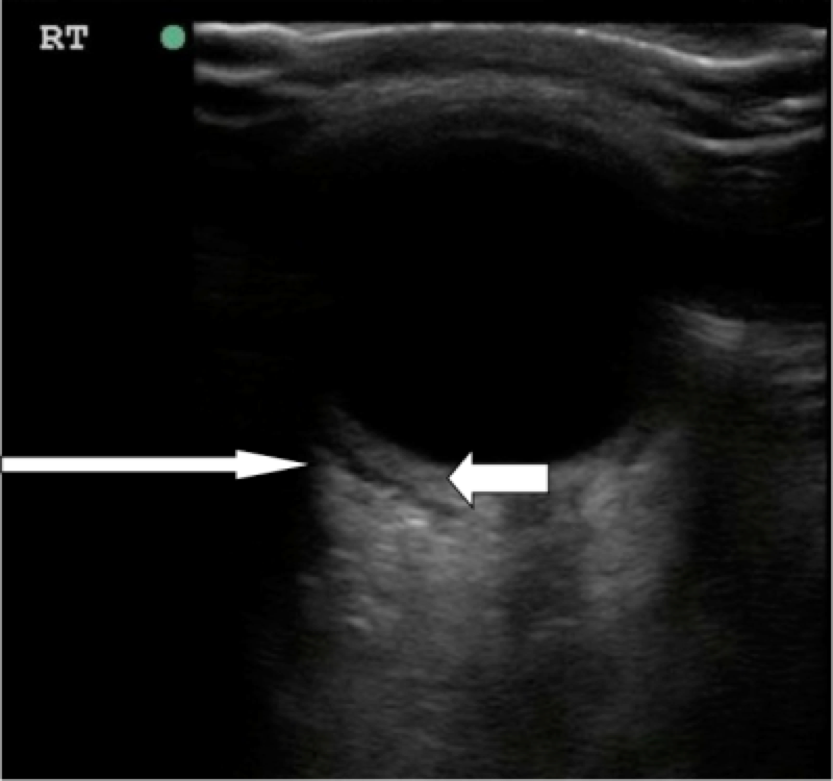

- Figure 10. Orbital cellulitis. Long arrow shows hypoechoic rim concerning for postseptal fluid tracking posterior to the globe. Short arrow shows thickening of the posterior segment of the eye.12 (Source: Seif D et al.13)